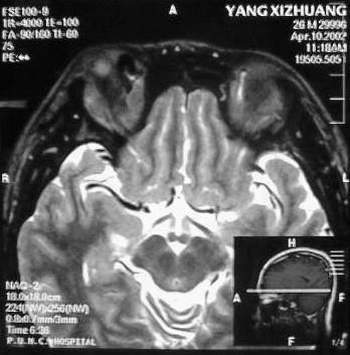

MRI及增强结果如下:

患者压颈及其它Valsava试验结果阴性。从MRI分析,在T1、T2、T+C检查该支血管均为明显流空现象,说明该血管血流速度很快,而从走行和分布看,眼上静脉可能性很大。也许也不能除外异常的眼动脉或异常血管。眶内主要可能的血管病变包括颈内动脉海绵窦瘘(高流窦)、AVM、眼眶静脉曲张、海绵状血管瘤、静脉性血管瘤、毛细血管瘤和眶内动脉瘤。。 1、颈内动脉海绵窦瘘:该患者临床有一部分支持该诊断。但从影像分析,海绵窦未见明显扩张;眼外肌未见明显充血扩张的长T1、长T2信号;颈内动脉海绵窦瘘常可见继发到血栓,可见到短T1、长T2的血栓信号。 2、眼眶静脉曲张:该疾患一般常见于小儿。该患大多数会出现Valsava试验阳性,间歇性突眼。不符合该患。影像学检查,于曲张静脉内常可见血栓和静脉石。所以不符合该患。 3、AVM:患者目前的影像学资料尚不全面,但可符合该诊断。临床上改病常见于30岁左右年轻人,单侧发病,于本患较符合。问题在于临床没有明确的血管杂音,似乎难以解释。 4、该患影像学与海绵状血管瘤差别很大,所以可基本排除此诊断。 5、静脉性血管瘤和毛细血管瘤:MRI中等T1、长T2信号,较易与本病鉴别。 6、眶内动脉瘤:我觉得患者并不能排除本病,但同样,由于波动性阴性,似乎也难以解释。 纵上所述:本人觉得,患者AVM可能性较大,同时不能除外眶内动脉瘤。 关于进一步检查,我觉得DSA价格过于昂贵。是否可先进行彩色多普勒检查,首先可以明确是静脉系统还是动静脉瘘抑或是动脉瘤。第二步,可进行MRA检查,可以清楚地显示海绵窦地相关关系,并可借此诊断或排除颈内动脉海绵窦瘘。如还需第三部检查,可进行MRV检查,对静脉系统进一步评价。三种检查总共的费用2000多圆,但给予我们的信息量已经很丰富了。 敬请各位医师提出自己的见解。 谢谢!